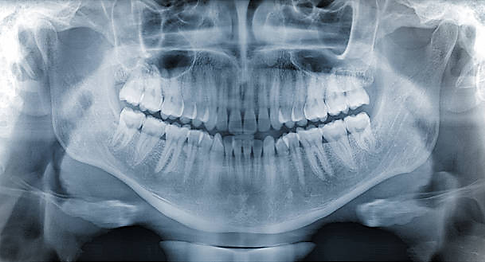

Ortopantomografía (panorámica): visión completa de dientes, huesos maxilares y articulaciones temporomandibulares.